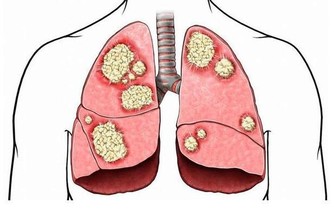

另外,對於糖尿病人來說,眼睛健康也是一個重要的關注點,因為他們的視網膜很容易會發生病變。

如果忽略對血糖的控制,可能最後,視力會變的非常差,看東西也模糊不清了。

但是如果血糖得到了一定控制,那麼視力可能會出現回升,也是不好說的,當血糖升至平穩時,視力也會得到改善。